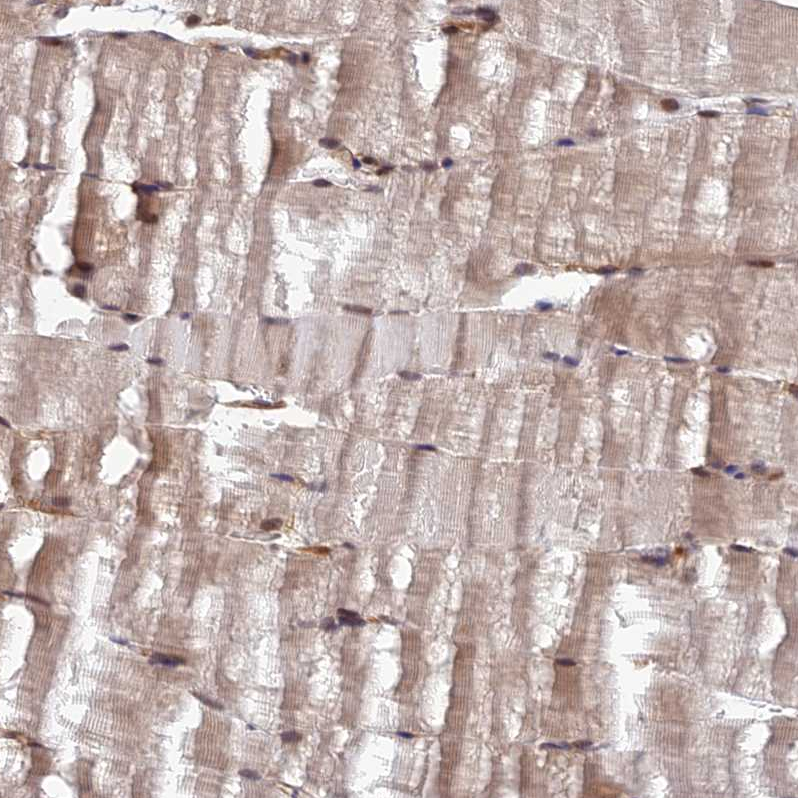

Immunohistochemical staining of human pancreas shows moderate cytoplasmic positivity in exocrine glandular cells.